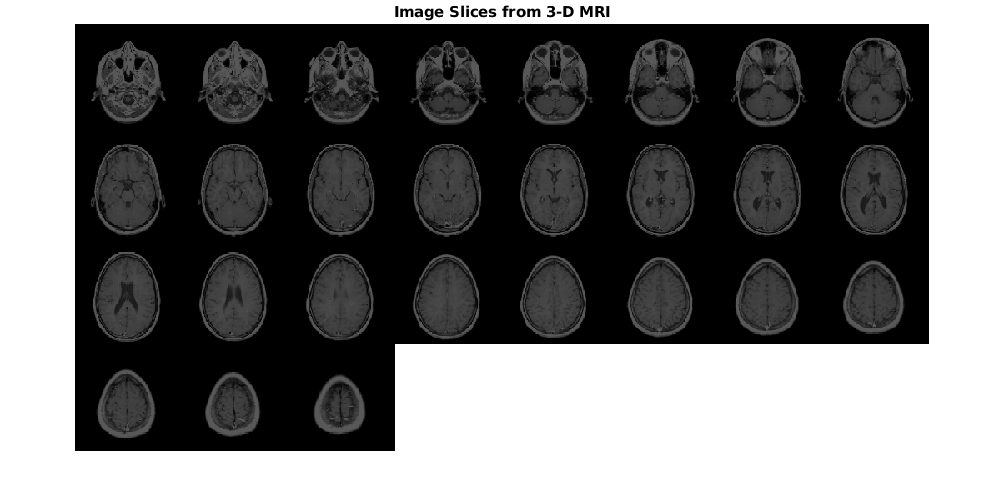

Отобразите фрагменты изображения от объема входа MRI как монтаж.

montage(mriVolume,'Size',[4 8],'BackgroundColor','w')

title('Image Slices from 3-D MRI','FontSize',14)

Отобразите фрагменты изображения от преобразованного объема MRI как монтаж. Срезы преобразованного изображения являются отражением входных фрагментов изображения через ось X.